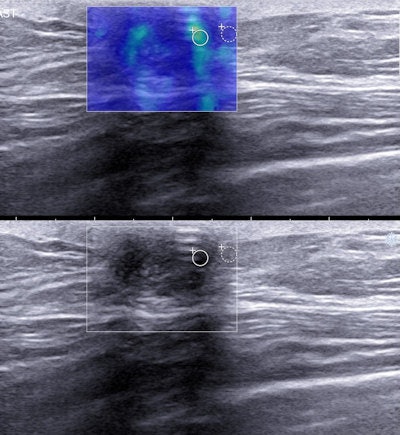

Elastography images of triple-negative breast cancers. They often demonstrate benign elastographic features, such as they are less stiff and have lower lesion-to-fat stiffness ratio than other invasive breast cancers. Image courtesy of Dr. Martina Džoić Dominković.Scarcity of research

The results demonstrate triple-negative breast cancers most commonly present as red (stiff), but a significant proportion of tumors appear as blue or green (soft), as well as orange. However, invasive cancers that are not triple-negative almost exclusively present as red.